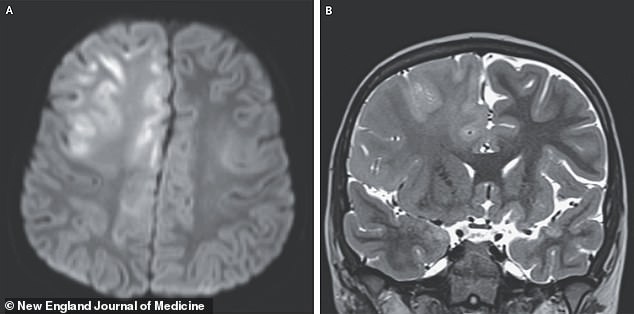

An MRI of his brain revealed a grim picture—swelling in the frontal lobe and corpus callosum, signs of cellular death. The diagnosis was SSPE, a progressive neurological disorder with a mortality rate of 95 percent. The boy, who had initially appeared healthy, succumbed to the disease a year after his symptoms began. His story, published in the New England Journal of Medicine, underscores the insidious nature of SSPE. It can take years to develop, its onset often delayed until a child is old enough to be in school or working, leaving families reeling with grief and medical bills.